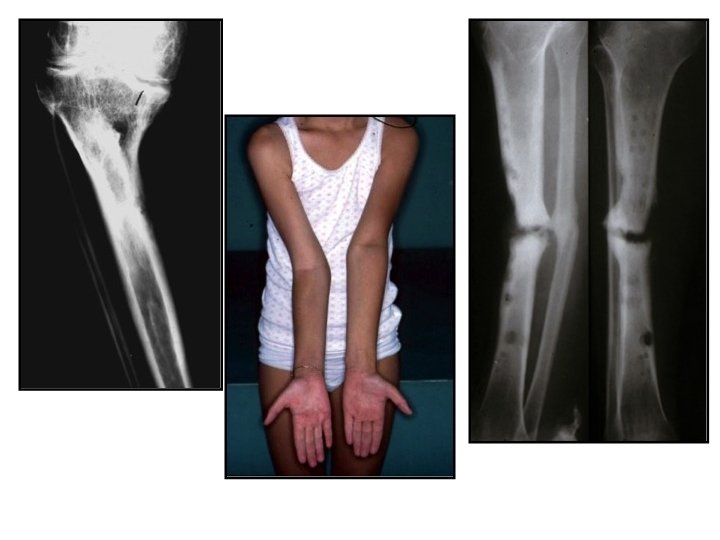

• Séquelles neurologiques, d’algodystrophie ou Sd de Volkmann – Raideur – Déformations – Etc. ……. . – Traitement difficile et aléatoire allant parfois jusqu’à l’amputation

Main radiale Volkmann Main ulnaire